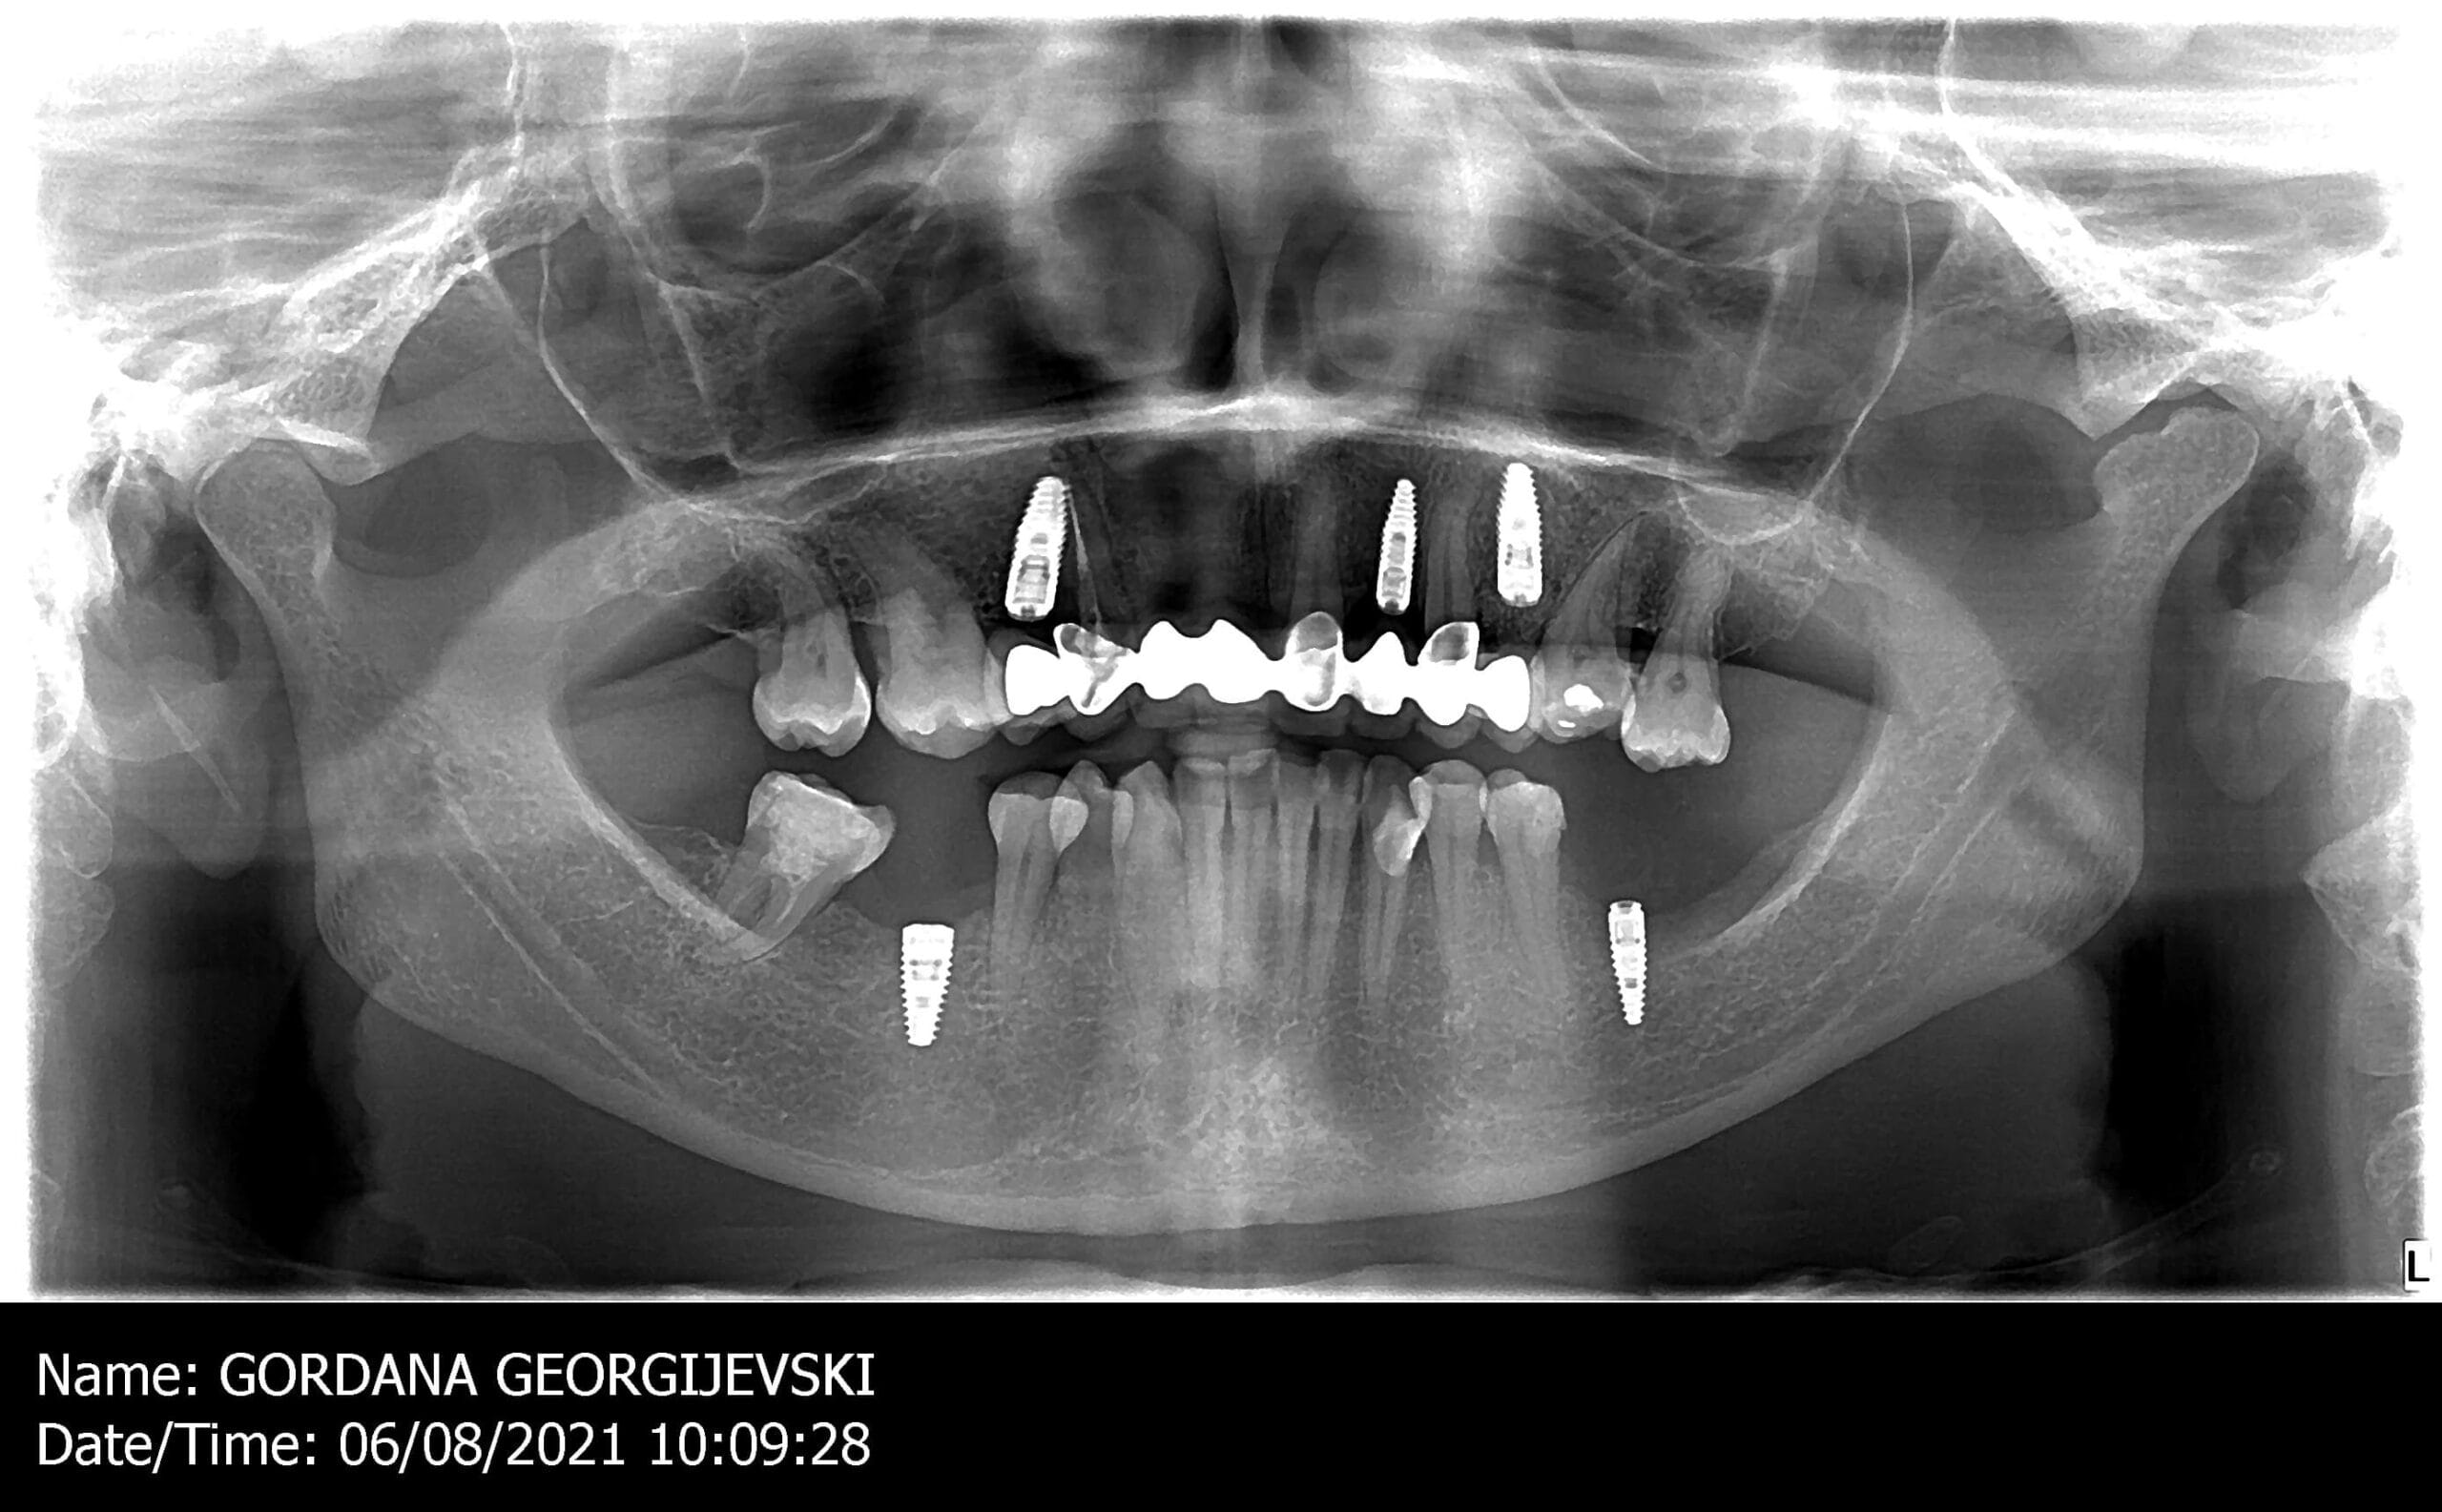

Prvo smo uradili snimak zuba da vidimo kakvo je stanje Gordaninih zuba i korenova. Nakon razgovora sa pacijentkinjom došli smo do zaključka da bi nedostajuće zube želela da nadoknadi implantatima. Zatim smo napravili 3D snimak kako bismo proverili da li ima dovoljno kosti za ugradnju implantata.

Nakon toga je usledio prvi klinički korak implantološko-protetske terapije – ugradnja implantata. U istom danu nakon ugradnje implantata izrađene su i privremene krunice.

Čekali smo 4 meseca da implantati potpuno srastu sa kosti, odnosno da se desi tzv. oseointegracija implantata.

Nakon perioda oseointegracije smo pristupili izradi definitivnih krunica od cirkonijum-keramike. Izuzetno smo vodili računa i o krunicama na implantima, koje su urađene na cirkonijum abatmentima.